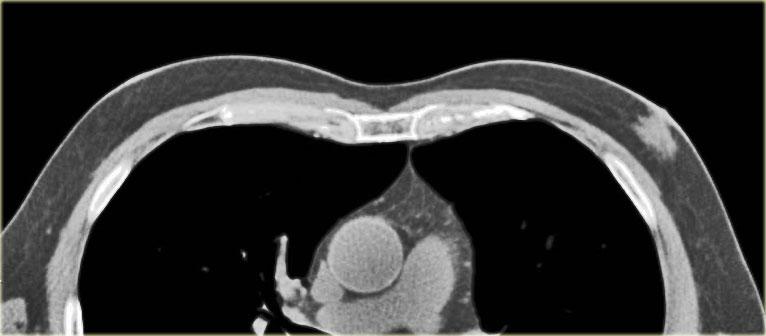

Bên trái là gynecomastia một bên.

Đây là phát hiện tình cờ trên CT được thực hiện vì một lý do khác.

Theo định nghĩa, gynecomastia là mô dưới quầng vú có kích thước từ 2 cm trở lên ở nam giới không béo phì.

Đây là một phát hiện ‘bình thường’ thường gặp, được ghi nhận ở 55% nam giới khi khám nghiệm tử thi.

Đỉnh tần suất mắc bệnh là ở độ tuổi 60 – 69.

Tình trạng này có ý nghĩa lâm sàng khi xuất hiện mới hoặc có triệu chứng.

Ở nam giới cao tuổi, gynecomastia chiếm 65% tổng số các tổn thương vú.

25% là ung thư và 10% là các tổn thương khác.